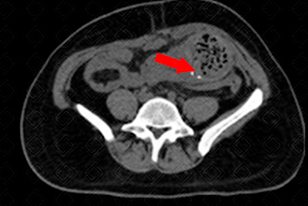

Texto alternativo para a imagem Créditos: Dra. Elazir Mota - Rio de Janeiro/RJ

Descrição das figuras : Tomografia computadorizada do abdome, sem administração do contraste venoso, evidenciando, na fossa ilíaca esquerda, presença de massa ovalada, com densidade de partes moles e contendo imagem linear, espontaneamente densa, podendo representar marcador de compressa retida (seta vermelha).

Exames de imagem: É de suma importância o radiologista ter conhecimento desse aspecto de imagem, para auxiliar no seu diagnóstico (figuras acima).

• Tomografia computadorizada (TC) do abdome ou tórax : Aspecto de uma massa heterogênea alongada contendo bolhas de gás e densidades metálicas intra-cavitária. A TC é o método de imagem mais eficaz para a detecção de um textiloma retido.